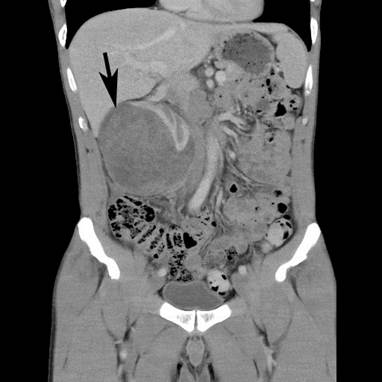

A 43-year-old Caucasian man, with a 4-week history of right upper quadrant and right flank pain radiating to his right testicle, presented to his general practitioner. There was no preceding trauma, haematuria or any other systemic symptoms. The past medical history included osteoid osteoma in the left upper femur, which was removed in 2007. He also had L4/5 microdiscectomy. There was no positive family history of medical problems or cancer. He was a non-smoker, had no allergies and was not taking any regular medications. The general practitioner organized an ultrasound, which revealed a large subcapsular haematoma measuring 7 × 5 × 7 cm in the right kidney compressing the renal cortex. Further investigation with computed tomography (CT) scan of the abdomen with intravenous contrast revealed enlarged right kidney with subcapsular haematoma and a mass lesion within the right lower pole measuring up to 7.4 × 7.5 × 9.2 cm with associated paracaval lymphadenopathy producing compression of the right renal vein and inferior vena cava (Figures 1 and 2). The patient was then referred to an urologist for further management.

Figure 1. CT scan – coronal view. Large mass lesion (arrow) within right kidney measuring up to 7.4 × 7.5 × 9.2 cm.

Figure 2. CT scan – coronal view showing right kidney mass with subcapsular haematoma (arrows).

Physical examination revealed that the right kidney area was filled, with minimal tenderness. The haemoglobin concentration was 140 g/L. There was a mild elevation of creatinine (116 μmol/L), and the estimated glomerular filtration rate was 66 ml/min. CT staging showed a large right renal tumour and significant paracaval lymphadenopathy producing compression of the right renal vein and inferior vena cava. The size of the tumour was substantially increased in size to 11.5 × 11.6 × 11.5 cm when compared with that in the previous CT scan.